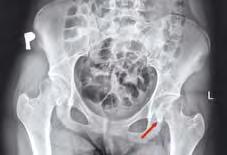

Badania obrazowe Badanie radiologiczne